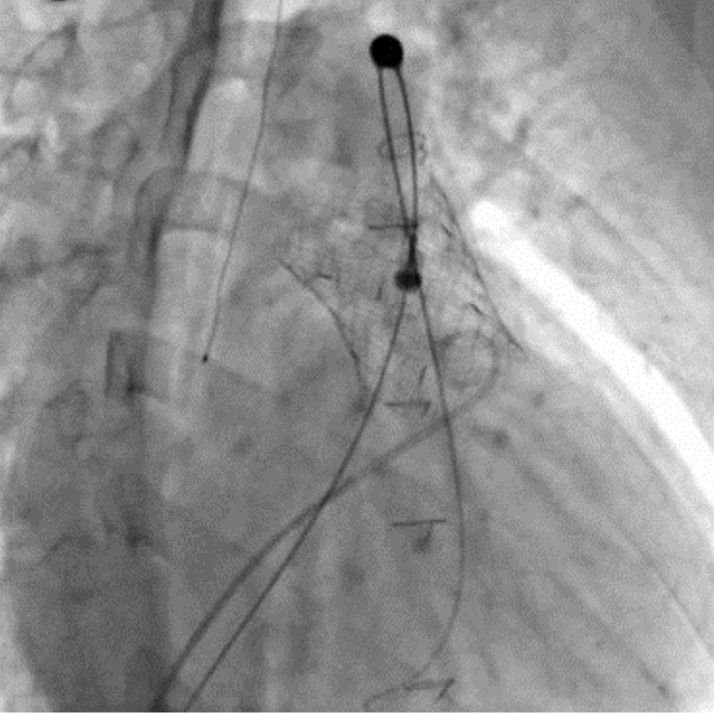

경피적 폐동맥판막 치환술(PPVI) 시술 장면. 서울대병원 제공

경피적 폐동맥판막 치환술은 가슴을 열지 않고 허벅지 정맥을 통해 카테터로 인공 판막을 삽입하는 최소 침습 치료법이다. 선천성 심장병 환자 중 폐동맥판막 기능이 저하된 경우 적용되며, 반복적인 개흉·개심수술을 대체하거나 수술 시점을 늦추는 치료 전략으로 활용되고 있다.